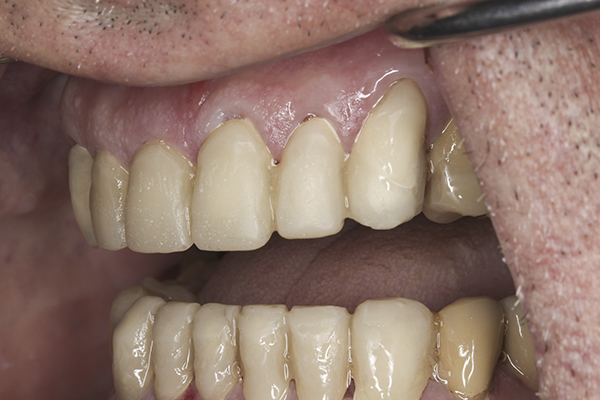

(6.) Preoperative right lateral, open view.

Figure 6

(9.) Preoperative right lateral, closed view.

Figure 9

(32.) Postoperative right lateral, open view.

Figure 32

(35.) Postoperative right lateral, closed view.

Figure 35